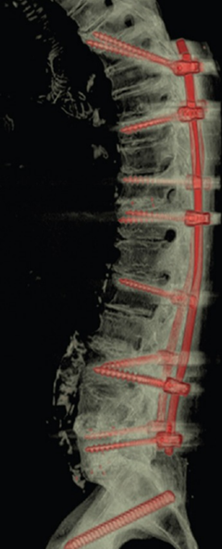

6.UIV固定区的杂交固定技术

横突钩的应用

移行棒(粗细棒)

骨水泥强化(UIV和UIV+1)

肋骨固定

棘间固定或动力稳定(UIV和UIV+1)

半坚强固定

多平面螺钉

减轻固定区上方的应力,实现固定区到非固定区的“软着陆”。

(1)横突钩和移行棒

图28-29 据文献报道,对于UIV应用横突钩和移行棒可以一定程度避免PJK/PJF的发生